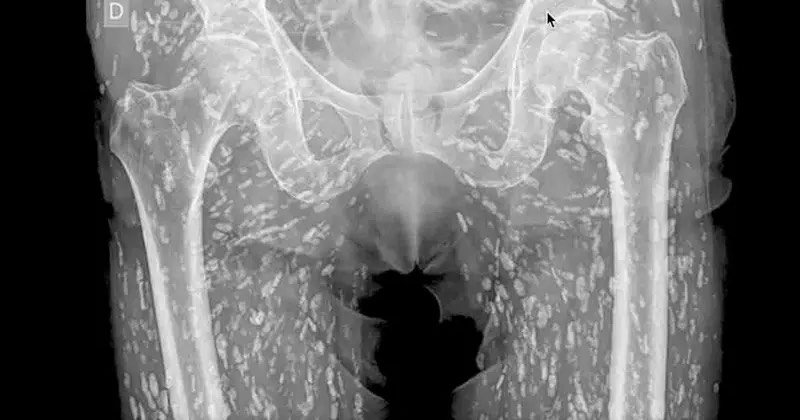

Inquietante radiografía muestra un cuerpo lleno de larvas

La Taenia solium ingresa al cuerpo humano a través de la ingestión de quistes larvales presentes en la carne infectada.